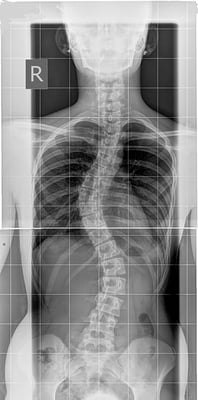

Bildlegende, von links: Röntgen mit Korsett, Röntgen von vorne/seitlich, Röntgen mit ausgeprägter Skoliose

Eine gewisse skoliotische Fehlhaltung (Krümmungen bis 10° Cobb) und geringe Skoliosen sind häufig. Es gibt jedoch keine Möglichkeit vorherzusagen, welche Skoliosen progredient werden. Aufgrund dessen sollten während des Wachstumsalters alle Skoliosen in regelmässigen Abständen von 4–6 Monaten ärztlich kontrolliert werden, skoliotische Fehlhaltungen bis zu 10° Cobb mindestens einmal jährlich.